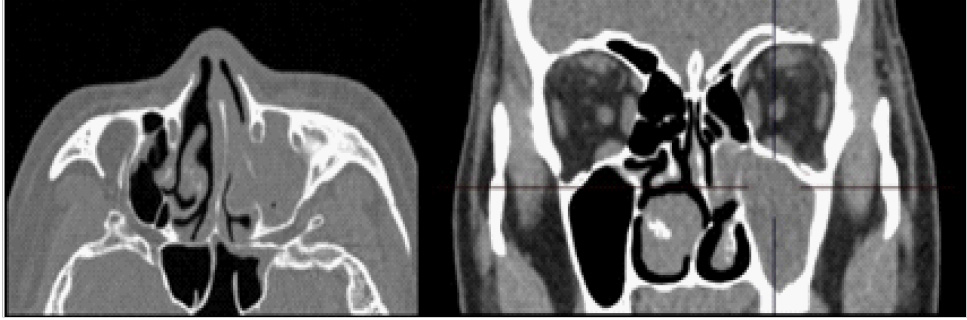

В заднем сегменте глазного яблока отмечалась дополнительная структура диаметром 8,5 мм, плотность 92 HU. В области сканирования левая верхнечелюстная пазуха тотально заполнена содержимым, ячейки решетчатой кости с субтотальным заполнением просвета (рис. 5).

Рис. 5. Компьютерная томограмма области околоносовых пазух